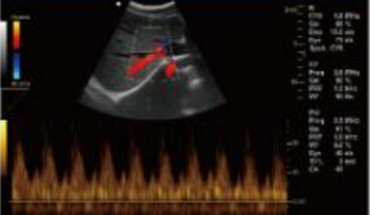

- B+CF (Images doubles)

- B+CF/DPDI+PW (Triplex)